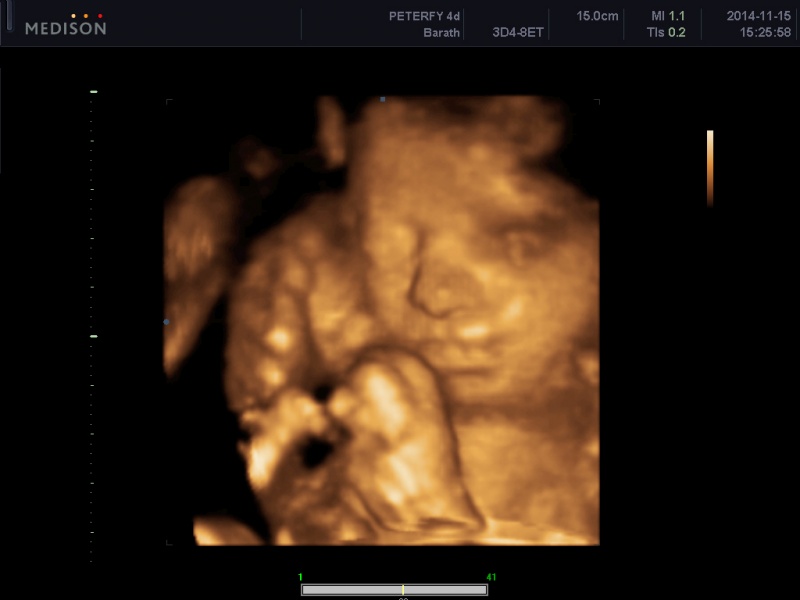

A genetikai UH mondjuk nagyon jó élmény volt. Legszívesebben már berendezném a babaszobát, vásárolnék mindent, (habár nem teszem mert tudom, hogy még felesleges) meg persze amíg nincs kész a lakás addig nem is tudnánk hova tenni a dolgokat.